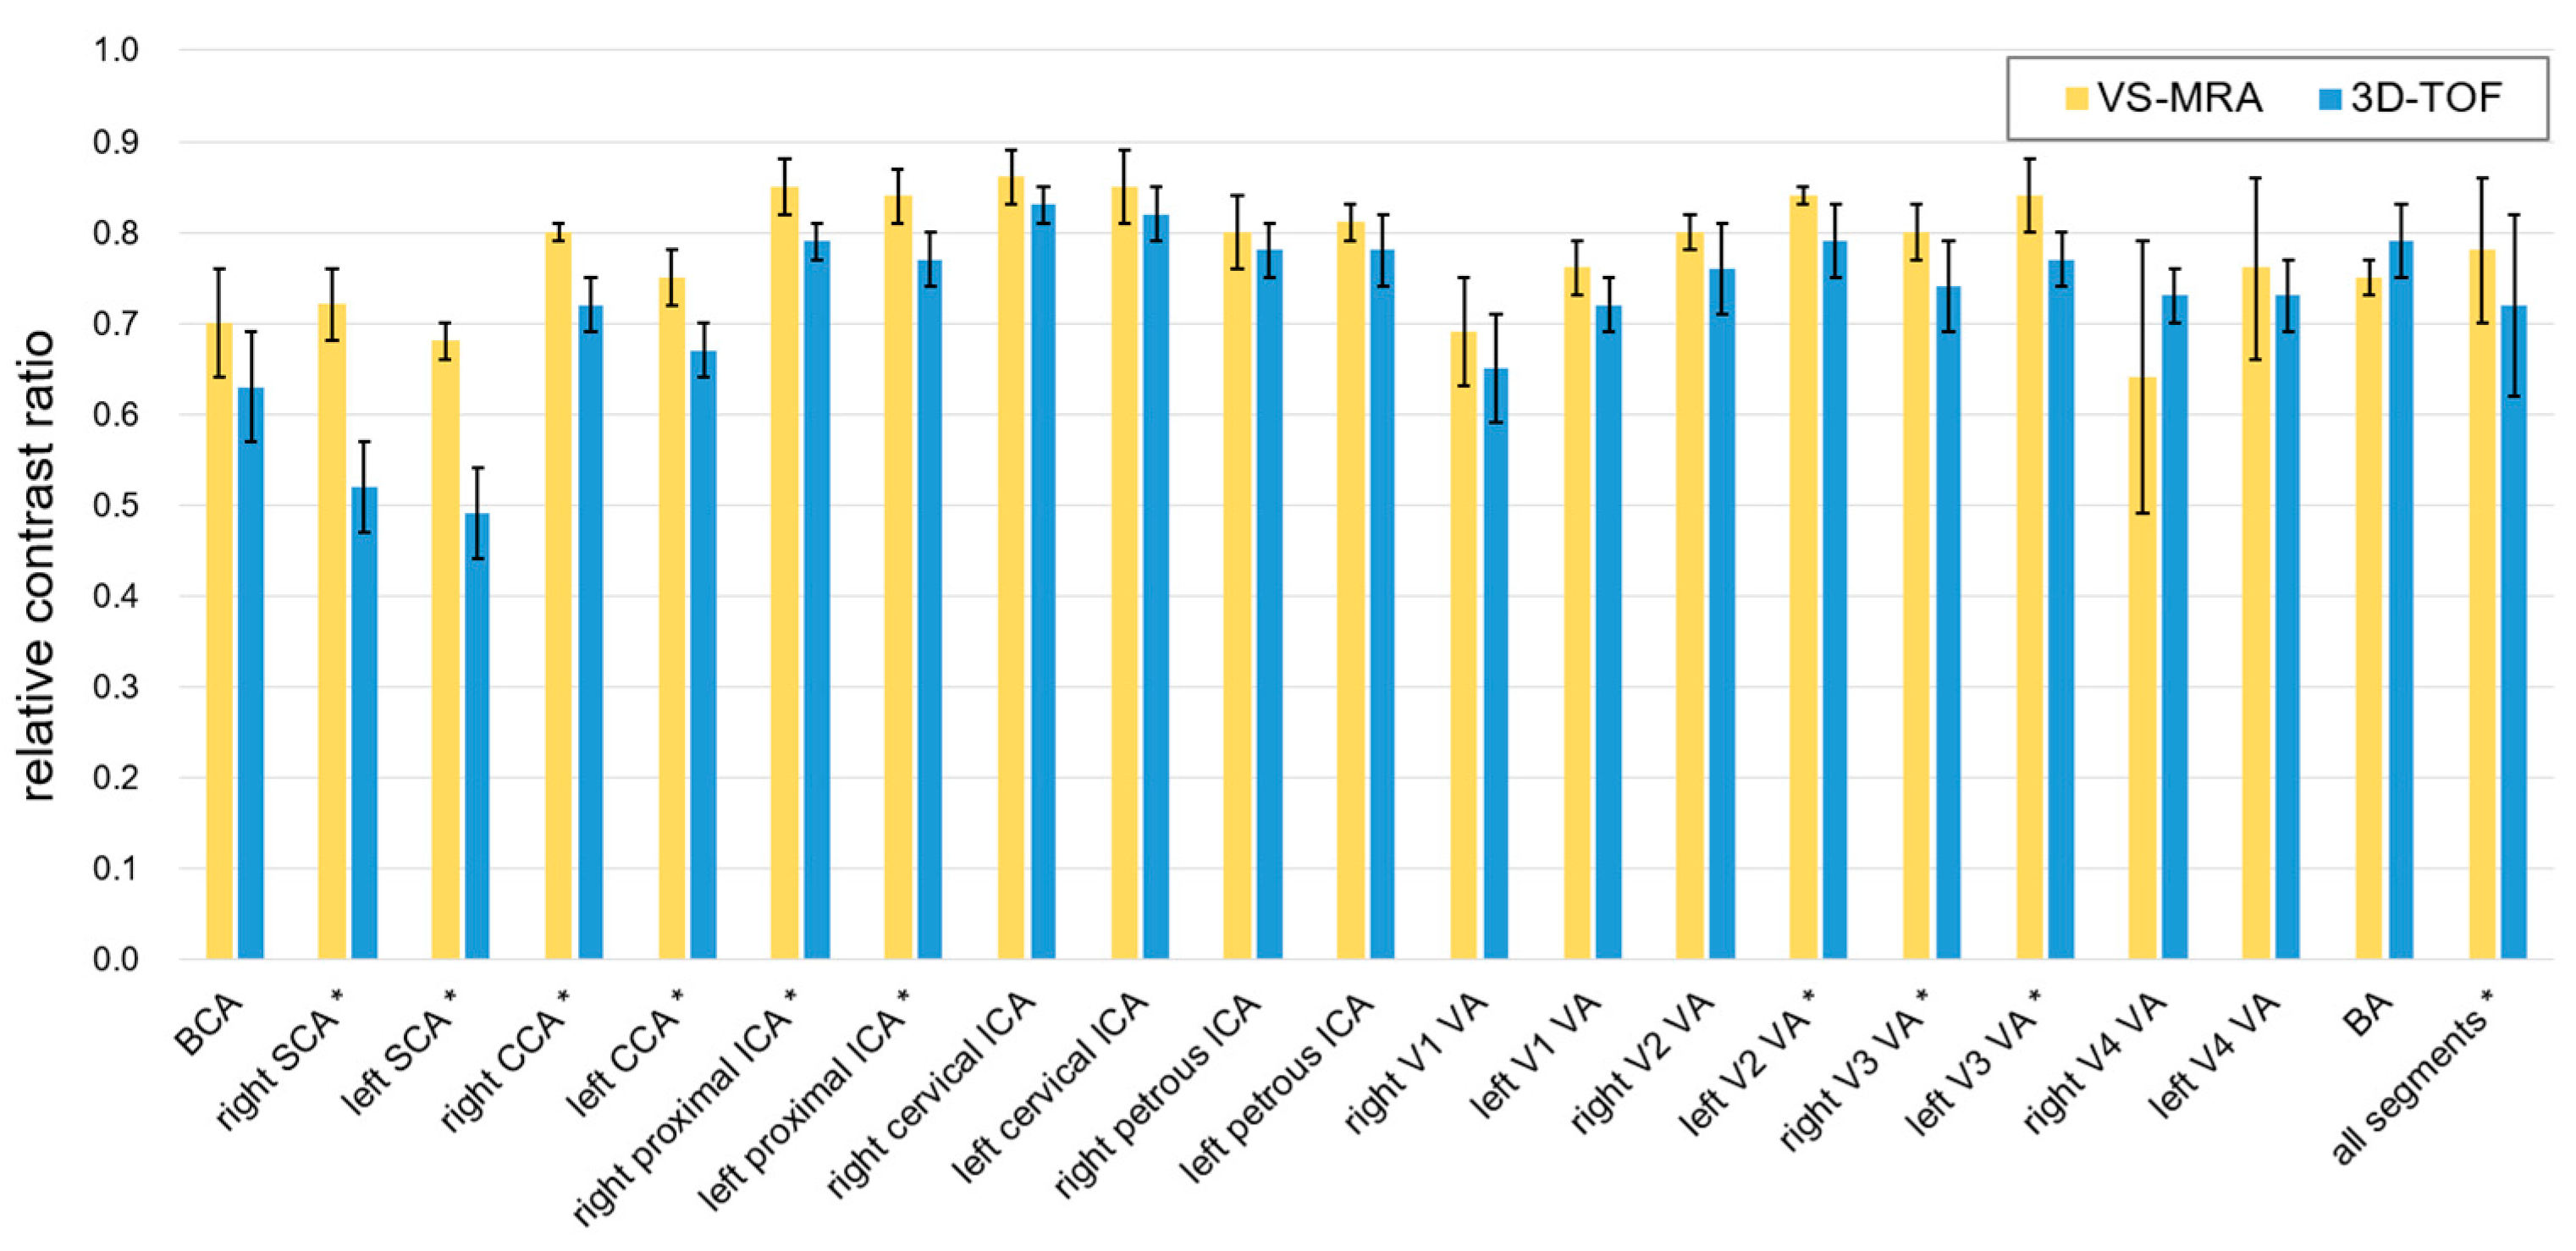

3. Results

4. Discussion